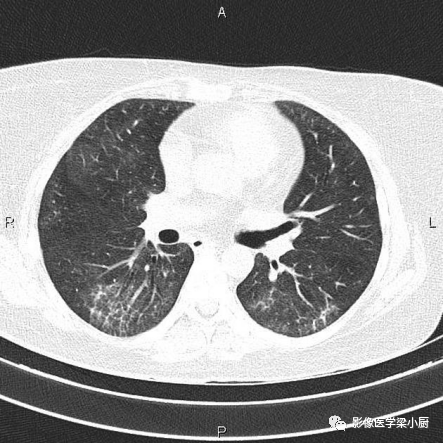

IPF患者牵拉性支扩

2.网格:网格影一般分布于两肺基底部、胸膜下,常伴结构扭曲。网格影不等同于小叶间隔增厚。

双肺底弥漫性网格状改变